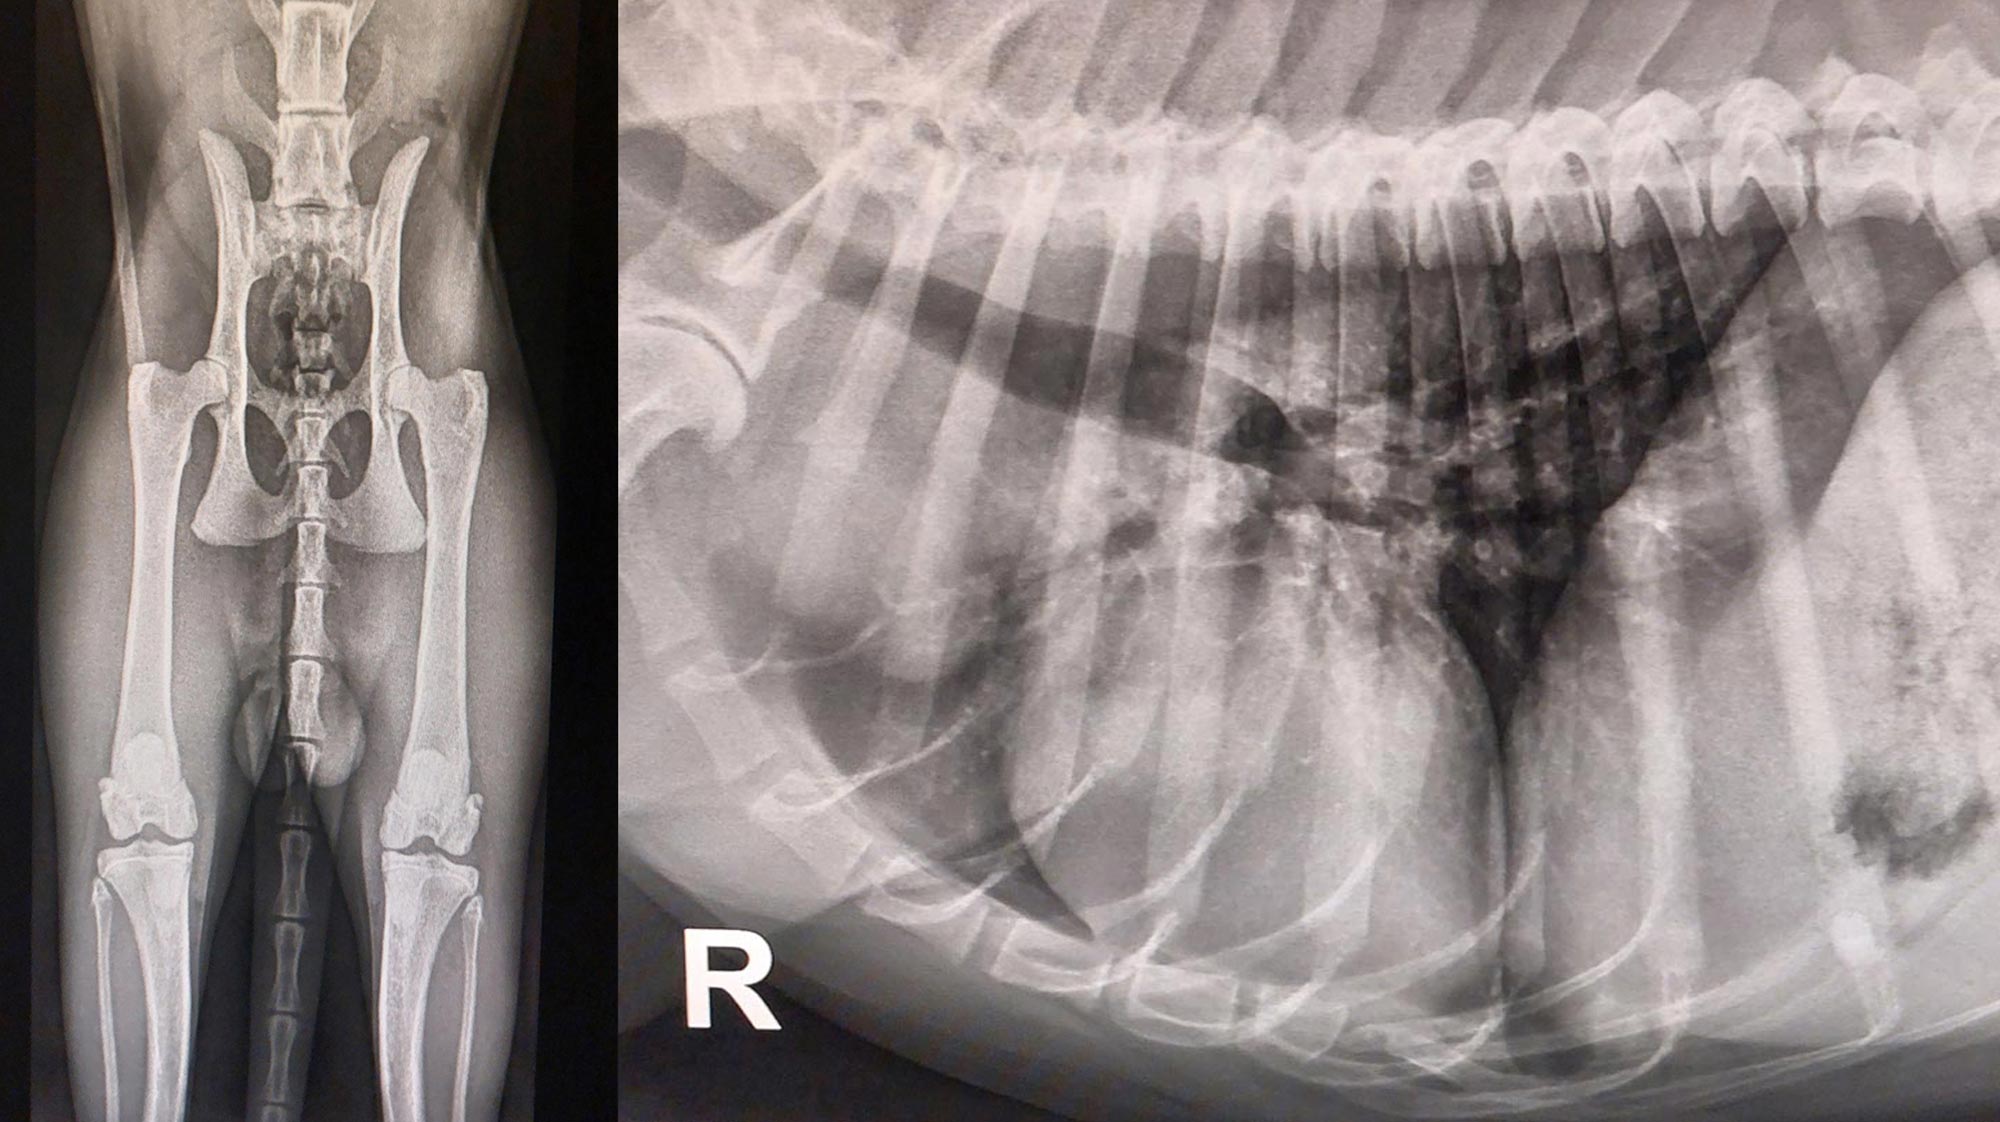

Digitales Röntgen

Wir verfügen über Digitales Röntgen, dem derzeit höchsten Niveau bei der Beurteilung von Knochenstrukturen. Durch die Digitalisierung ist zudem ein Versenden der Röntgenbilder per E-Mail an den Haustierarzt und an die Besitzer möglich.

Orthopädie

Ein wichtiges Instrument in der Orthopädie ist das digitale Röntgen. Lahmheitsdiagnostik am wachen Patienten als auch Untersuchungen unter Ultrakurzzeitnarkose wird ergänzt durch unseren Bereich der Orthopädischen Chirurgie. So führen wir Operationen wie z. B. TTA (Tibial Tuberosity Advancement) bei Kreuzbandrissen, Toggle Pin bei Luxationen des Hüftgelenks, Bandersatz und Reparatur bei Rissen und Ruhigstellungen von Gelenken mittels externem Fixateur durch.